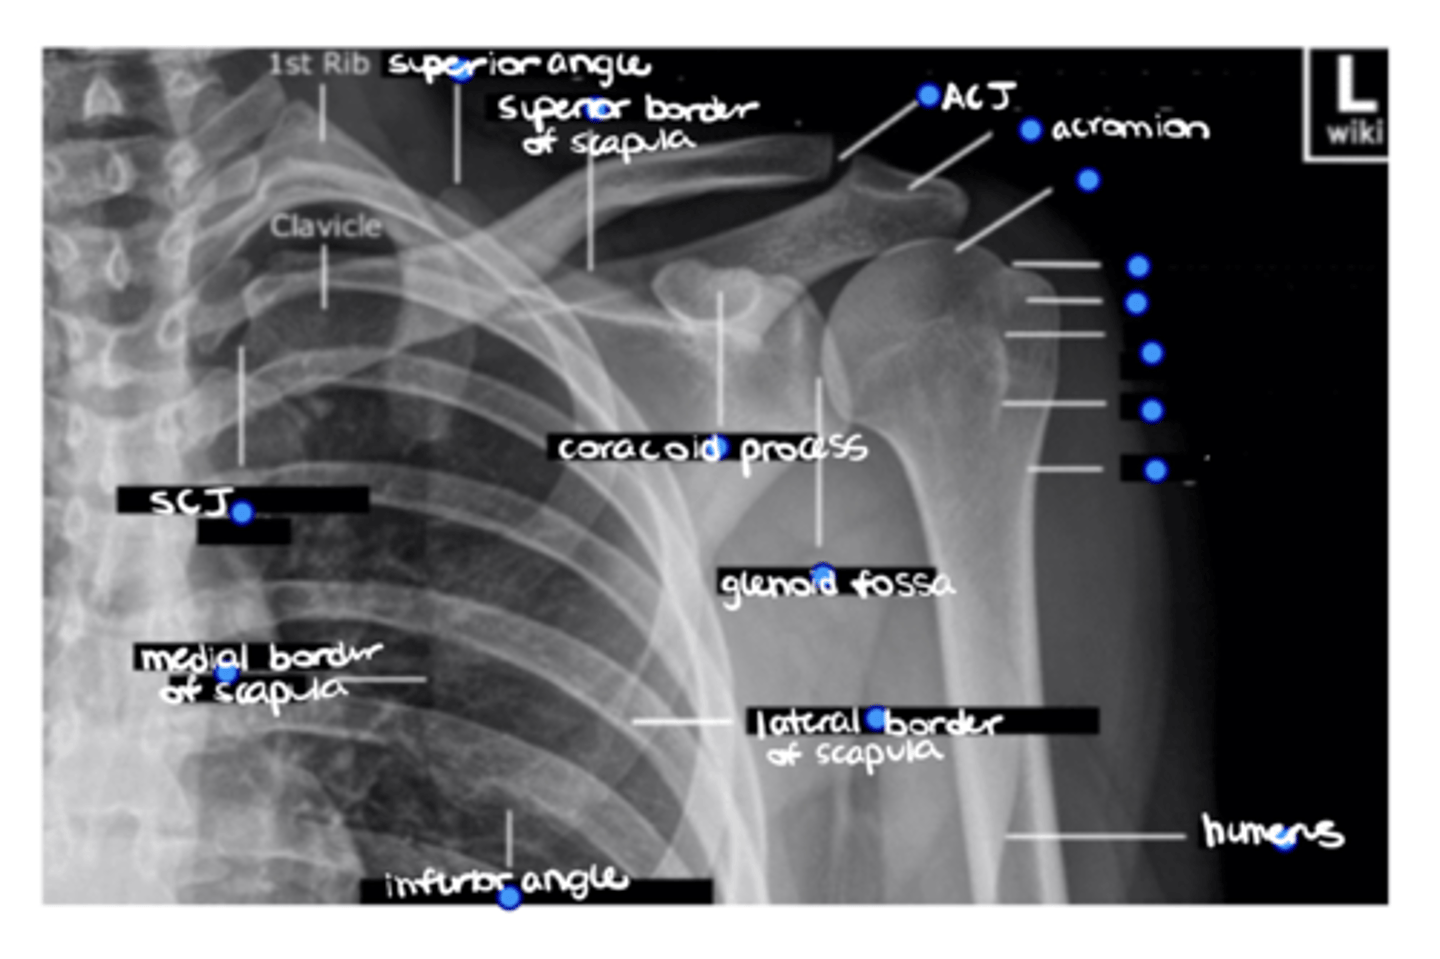

Superior angle of the scapula

ID the missing structure.

Superior border of the scapula

ACJ

Acromion